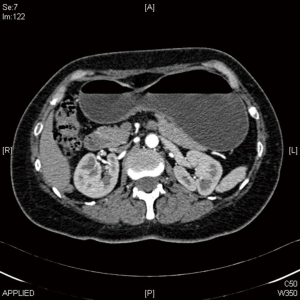

Early stage gastric cancer patients are fit for totally laparoscopic uncut Roux-en-Y gastrojejunostomy after distal gastrectomy. In the present video (Figure 1), the patient is a 61 years old woman who was diagnosed moderately differentiated adenocarcinoma of antrum by gastroscopy and histological test (Figure 2). The tumor stage was assessed to be cT1N0M0 by CT scan preoperation and EUS (Figures 3,4).